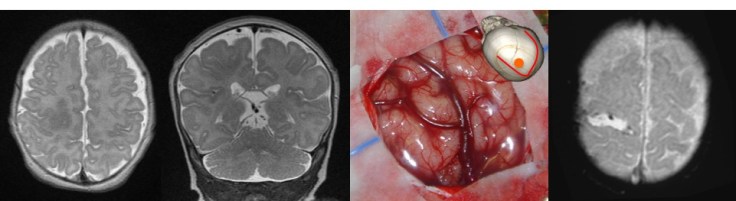

dysplasie corticale en région centrale chez un nourrisson de 5 mois ; noter la myélinisation précoce favorisée par l’activité épileptique ; résolution des crises et absence de déficit en post-opératoire.